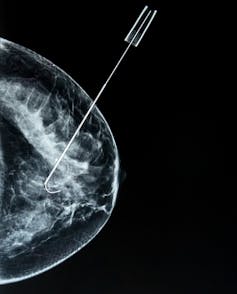

Genetic analyses of a sample of the tumour, also referred to as a biopsy, are becoming standard care in pathology departments. However, a biopsy only provides a snapshot of genomic changes on that particular piece of tumour. A biopsy also commonly requires an invasive surgical procedure, so cannot be performed frequently.